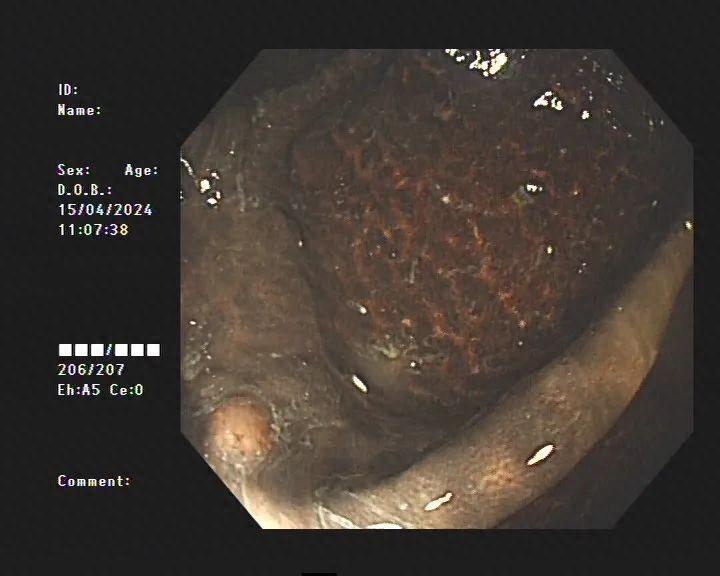

不查不知道,一查吓一跳!患者整条大肠内壁呈现棕黑色蛇皮样的改变,黑色素沉着明显,诊断为“结肠黑变病”,若继续发展,有癌变的可能。

据医生介绍,临床上许多患者自行口服药物后筛查肠镜均有不同程度的结肠黑变病。正常的结肠黏膜就像我们的口腔黏膜一样,是淡红色的,看起来光滑平坦,黏膜表面的小血管纹理清晰可见。而结肠黑变病的肠黏膜色泽呈现棕色、褐色,有豹纹或者蛇皮一样的条状纹,严重的甚至会变成黑色。

结肠黑变病患者

结肠黑变病是因为结肠壁的吞噬细胞吞噬了褐色素样物质,导致肠壁色素沉着。通俗点说,就是大肠吃多了色素,就变成了黑肠。此外,直肠前突、肠套叠、溃疡性结肠炎等其他疾病也可能导致黑变病。

虽然结肠黑变病属于非炎症性、良性、可逆性疾病,但一般来讲,结肠黑变病合并肠癌、肠息肉的概率很高。严重时,甚至需要手术治疗。